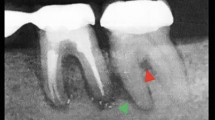

Introduction Bisphosphonates and denosumab reduce the risk of skeletal events in some malignancies (for example, breast, myeloma). These drugs carry a significant risk of a difficult-to-manage side effect of medication related osteonecrosis of the jaw (MRONJ). Preventive dental screening and treatment reduces the incidence of MRONJ. A managed clinical network (MCN) has been used to provide a MRONJ risk reduction pathway. A 360 degree survey was undertaken to assess the effectiveness of the pathway.